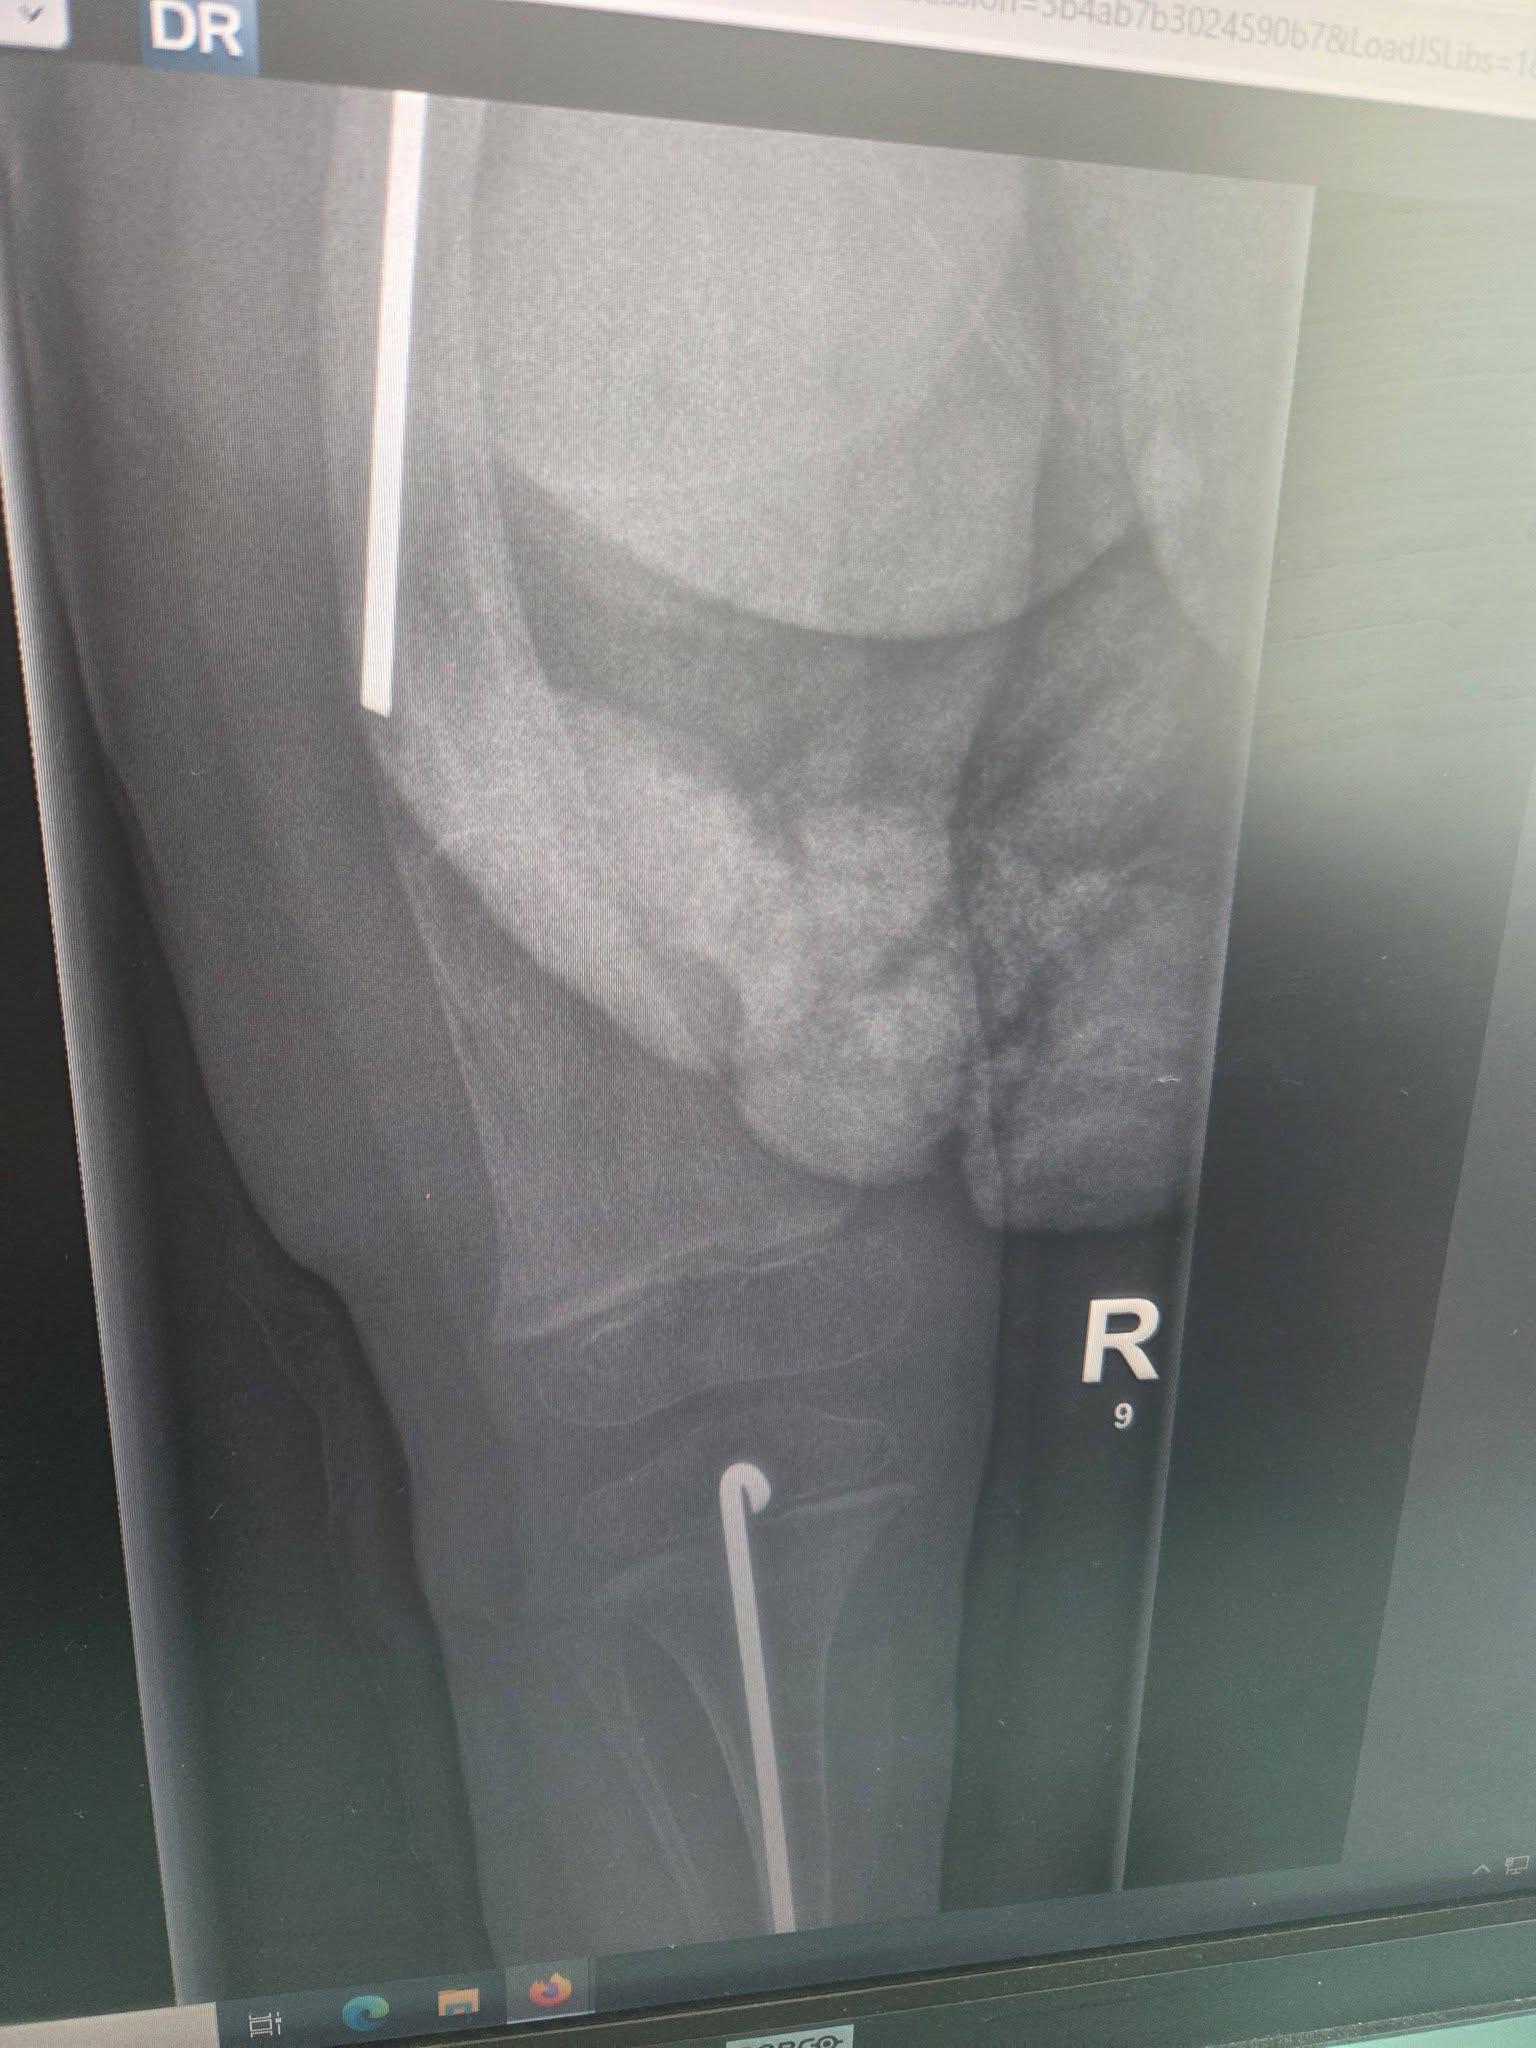

Madzia choruje na wrodzoną łamliwość kości typu III (osteogenesis imperfecta) – rzadką, genetyczną chorobę tkanki łącznej, która powoduje skrajną kruchość kości. Złamań doznała już w życiu płodowym, a jej organizm nie produkuje kolagenu. Choroba jest nieuleczalna, a leczenie ma charakter objawowy i obejmuje stałą rehabilitację, liczne operacje, stabilizację kości oraz specjalistyczną farmakoterapię. Dziewczynka ma za sobą już kilka poważnych zabiegów oraz kilkanaście podań leków wzmacniających kości. Przed nią kolejne operacje i intensywna fizjoterapia, bez której trudno byłoby myśleć o większej samodzielności.